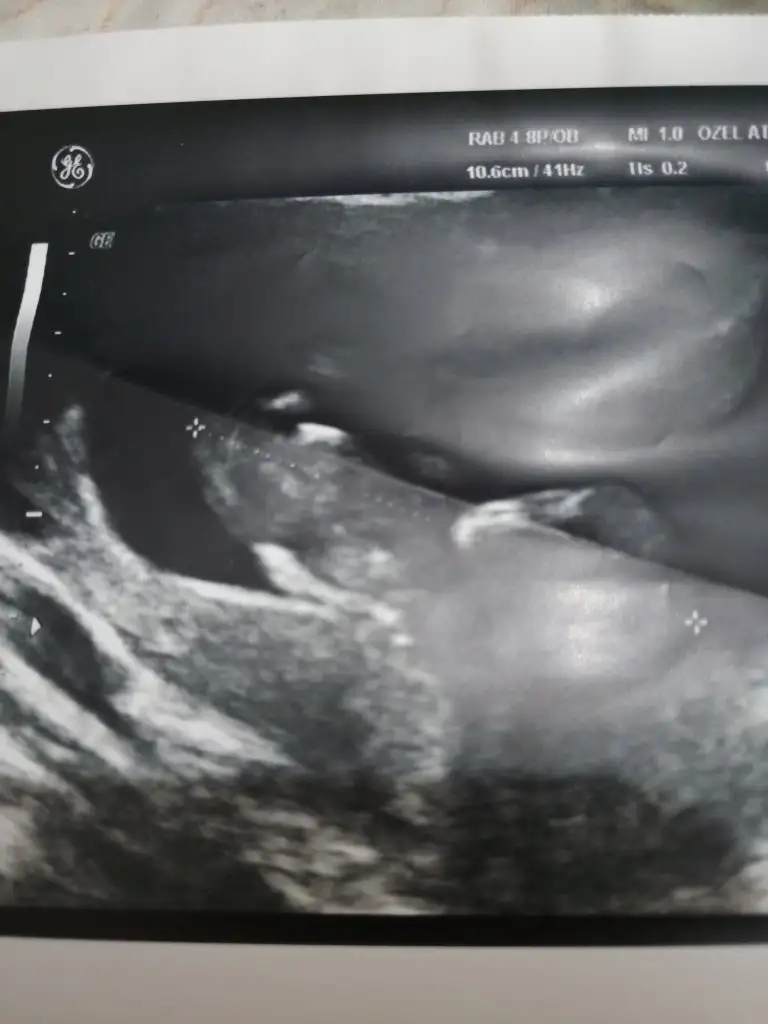

Net degil sanki kız gibi ama kafada erkek şekliDiğerinde hiç net degıldır ama atim Eki Görüntüle 2574696

Bu vajinal sagda görünüyor asıl solmuş ve buna göre erkekEki Görüntüle 2574901 bu vajinal bakılan düşük riski olduğu için vajinadan bakıldı

Daha önce ne dedim bilmiyorum burada nub paralel görünüyor kız gibi 12+ usg olursa paylaşınEki Görüntüle 2574907 Eki Görüntüle 2574908 Eki Görüntüle 2574909 Canım 11+1ız sabah dayanamadık doktora gıttık.cınsıyetı bellı degl ama eşim cok merak edıyor sor bakalım dıyor nub a göre neymıs cınsıyetı dıyebıze tekrar bakarsan cok sevınırım

11 yada 12 hafta tekrar paylaşırsınız şimdilik erkek ama 12 hafta tahminimi onaylarız

Erkek olduğunu tahmin ediyorum